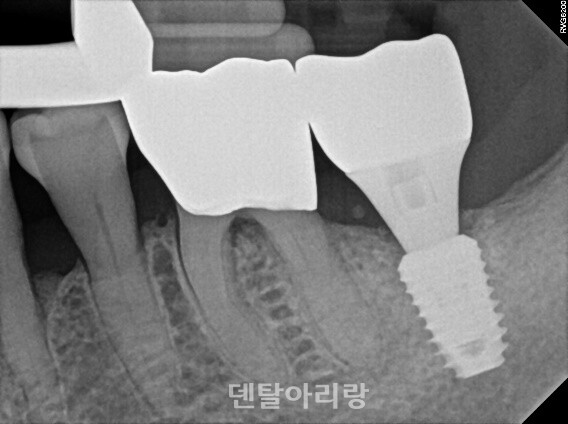

상악동 점막을 골점막(mucoperiosteum)이라 불리기도 하는데 조직학적으로 상악골과 하악골의 골막과는 다르고 상악동점막과 주변골사이에 골모 세포가 없기 때문에 아직 논란의 여지가 있다. 다만, 최근 여러 연구를 통해서 상악동 점막에 의한 골유도능력이 관찰되어 보고되기도 하였다. 실험을 통해 상악동 점막의 거상하여 골이식재 없이 거상 부위에 혈액과 임플란트만 식립하고 경과 후 현미경으로 분석한 결과, 임플란트 주변으로 신생골이 형성된 것을 관찰할 수 있었다(Clinical Implant Dentistry and Related Research, Volume 8, Number 1, 2006)<그림 17, 18>.

△그림 17. 상악동 점막 거상 후, 혈액이식 및 임플란트 식립

△그림 18. 상악동 점막에 의한 임플란트 주변 신생골 형성0

앞으로도 상악동 점막에 대한 연구가 더 필요하나, 확실한 것은 건강하고 손상되지 않은 상악동 점막은 상악동 골이식술 예후에 매우 긍정적인 영향을 미친다는 것이다.